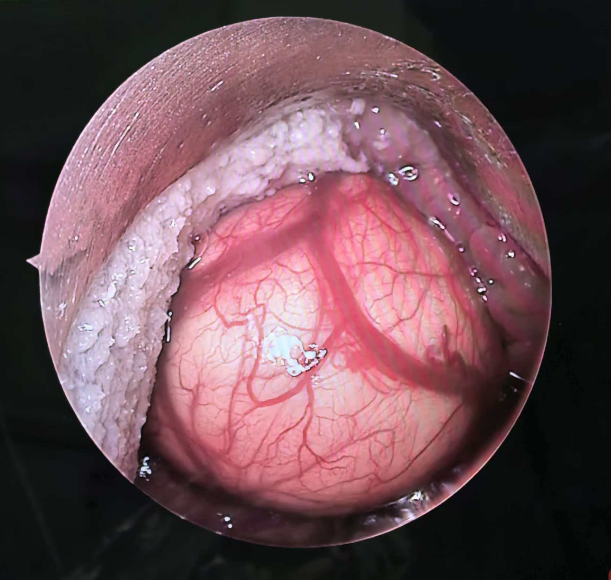

五官科:微创手术切除会厌囊肿疗效显著

毕业于广州中医药大学中医学专业,擅长耳鼻喉科多种常见病的诊疗,熟练掌握鼻内窥镜下治疗鼻中隔偏曲,鼻息肉,慢性鼻窦炎,耳前瘘管,声带息肉,慢性扁桃体炎等手术操作。对耳鼻喉术后康复也具有相当经验。